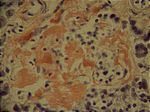

Amyloidose Langerhans-Inseln, Ko.